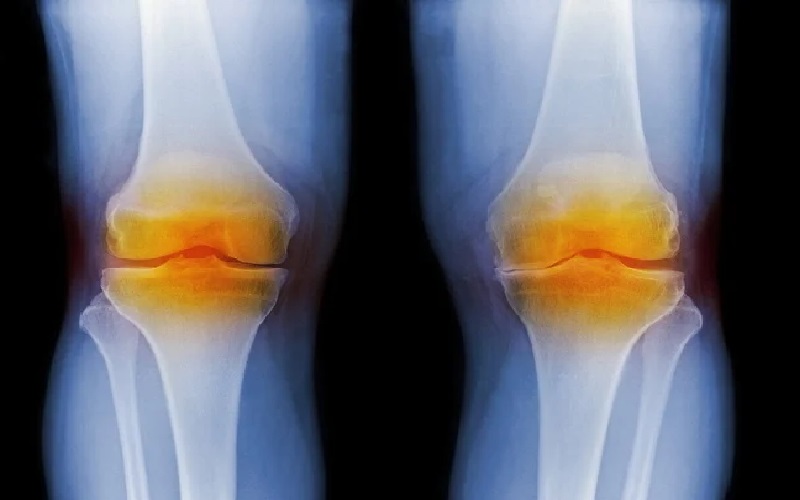

بنسبة 100%.. الذكاء الاصطناعي يشخص هشاشة العظام بدقة

نيسان ـ يمكن لاختبار جديد، طوّره باحثون من كوريا الجنوبية، مدعّم بالذكاء الاصطناعي تشخيص هشاشة العظام والتهاب المفاصل الروماتويدي بدقة تصل إلى 98.1% باستخدام عينة صغيرة فقط من سائل المفصل (الزليلي).